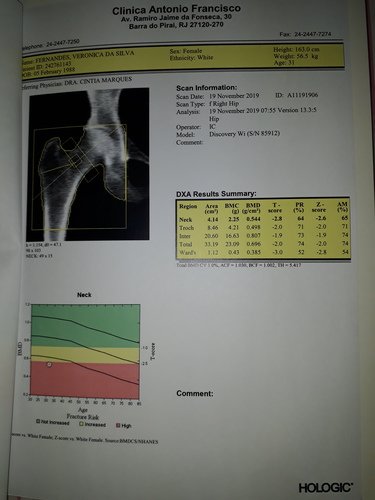

Osteoporose